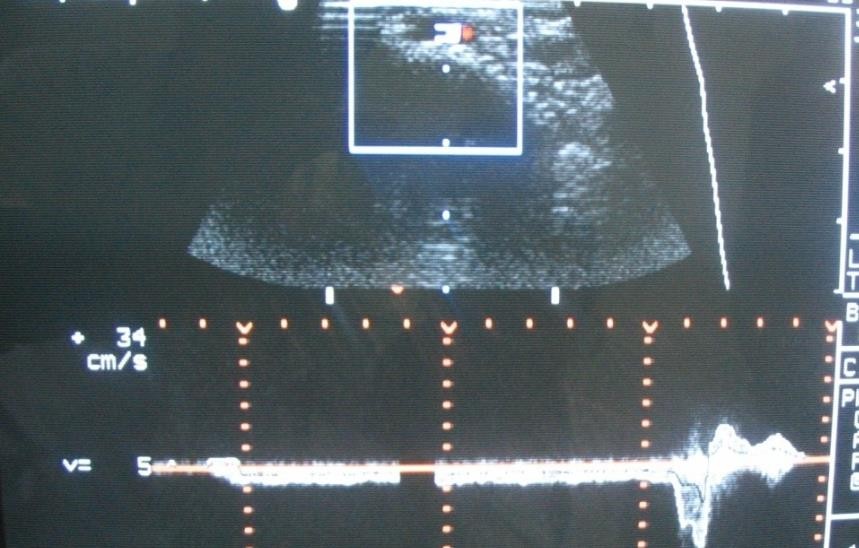

Doppler sonographic studies were conducted to assess testicular blood circulation and determine the hemodynamic type of varicocele. This allows for the identification of qualitative and quantitative characteristics of testicular blood circulation. Visually, it is possible to detect a decrease or increase in blood flow zones.Ultrasound scanning of the testicular vessels is a complex and time-consuming procedure. The difficulties were primarily related to the contraction of the muscle that lifts the testicle, the inability to precisely hold the sensor due to the use of gel, and the variability of the anatomical features of the testicular vessels.This method allows for non-invasive determination of linear blood flow velocity and the viability of anastomoses in dynamics after surgery. It also helps to determine the rate of reverse flow along the spermatic vein using the Valsalva maneuver (Figures 1, 2). | Figure 1. Testicle in longitudinal section with its dimensions marked: a - length, b - transverse dimension |

| Figure 2. Blood backflow curve |

When using Doppler methods, we considered it important to study the blood flow velocity in the testicular vessels, the degree of blood backflow through the seminal veins in the pampiniform plexus at rest and during straining. Studies were conducted in standing and lying positions. The obtained vascular Doppler waveforms were evaluated qualitatively and quantitatively. Attention was paid to the characteristics of blood flow velocity, while the absolute value of blood flow velocity was not taken into account. We focused on the shape of the Doppler waveform, considering the distribution of Doppler frequencies and the direction of blood flow. It is important to assess the quantitative characteristics of blood flow, and the evaluation of blood flow was informative, taking into account both the true parameters and the calculated indices.